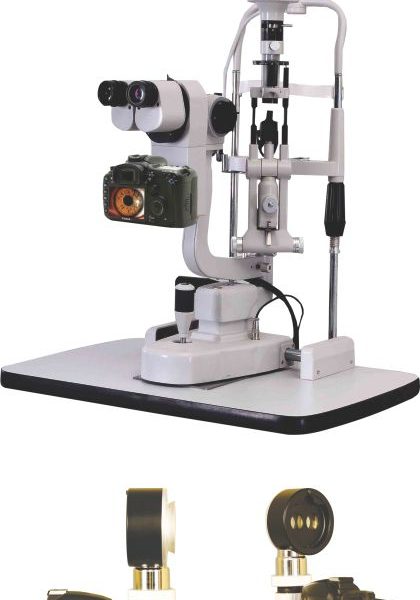

MCC-500MD

HD C-Mounts

January 8, 2018Slitlamp Imaging

HD-Image- Capturing

Slitlamp Imaging

Using a beamsplitter, SLR mount and a DSLR camera capture in 18MP (or higher) to get a superior quality image perfect for patient data collection, review and HD live display. Record video clips in full HD.